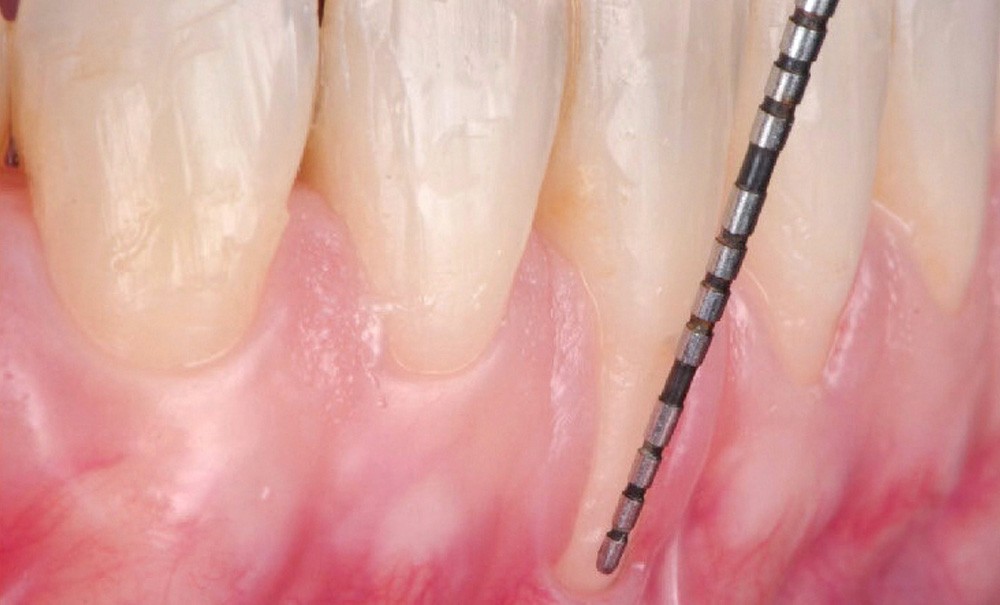

L’analyse du phénotype parodontal met en évidence une gencive fine et transparente (phénotype fin), associée à une bande kératinisée réduite, voire absente. Le sondage parodontal confirme la stabilité du parodonte. La récession la plus profonde, observée sur la dent 41, mesure 6 mm (fig. 1b).